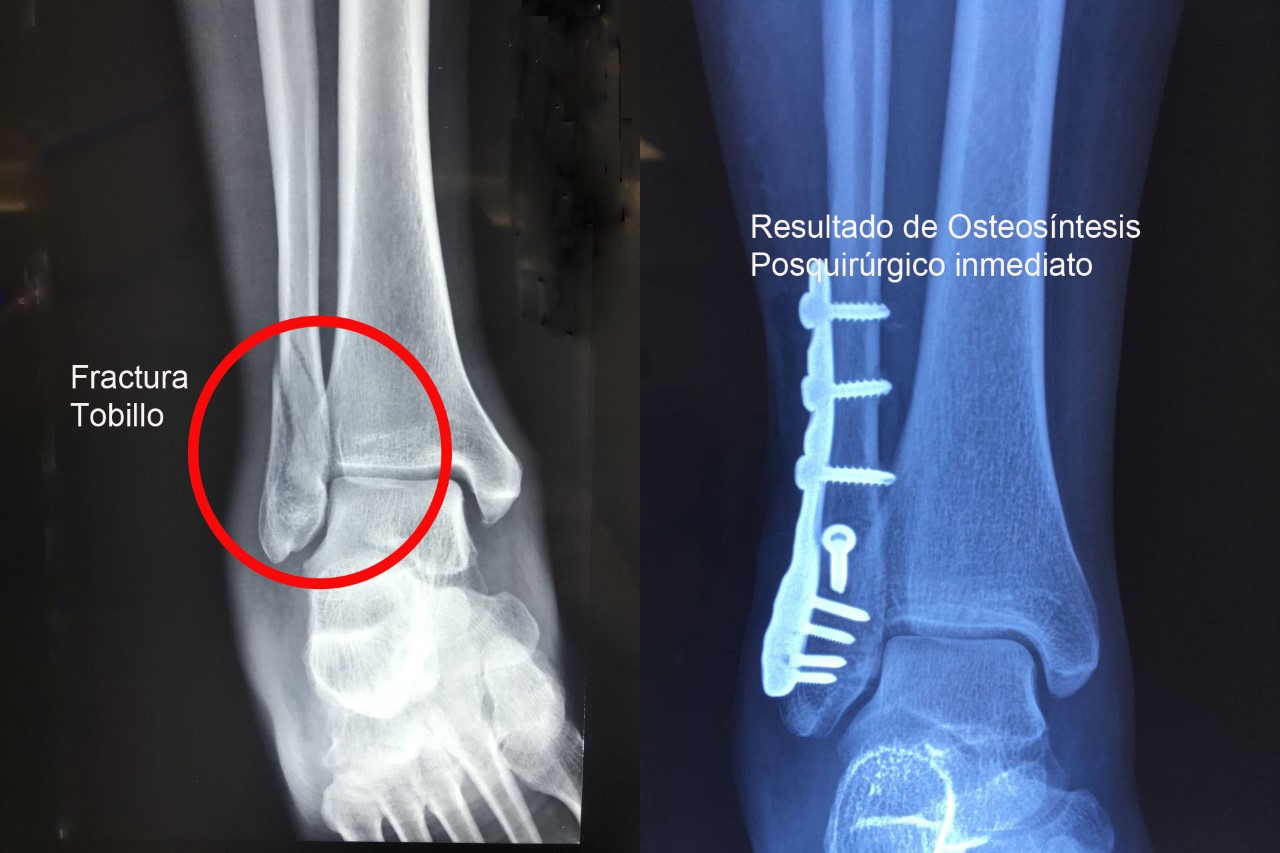

Una fractura ósea es la ruptura de un hueso, la cual puede presentarse por diversas causas y su tratamiento dependerá de la magnitud, sitio anatómico y de las enfermedades concomitantes. Algunas pueden manejarse de forma conservadora con solo inmovilización y hay otras que requieren de un tratamiento quirúrgico. A continuación, podrá ver algunos casos quirúrgicos, dando clic a la zona del cuerpo afectada.